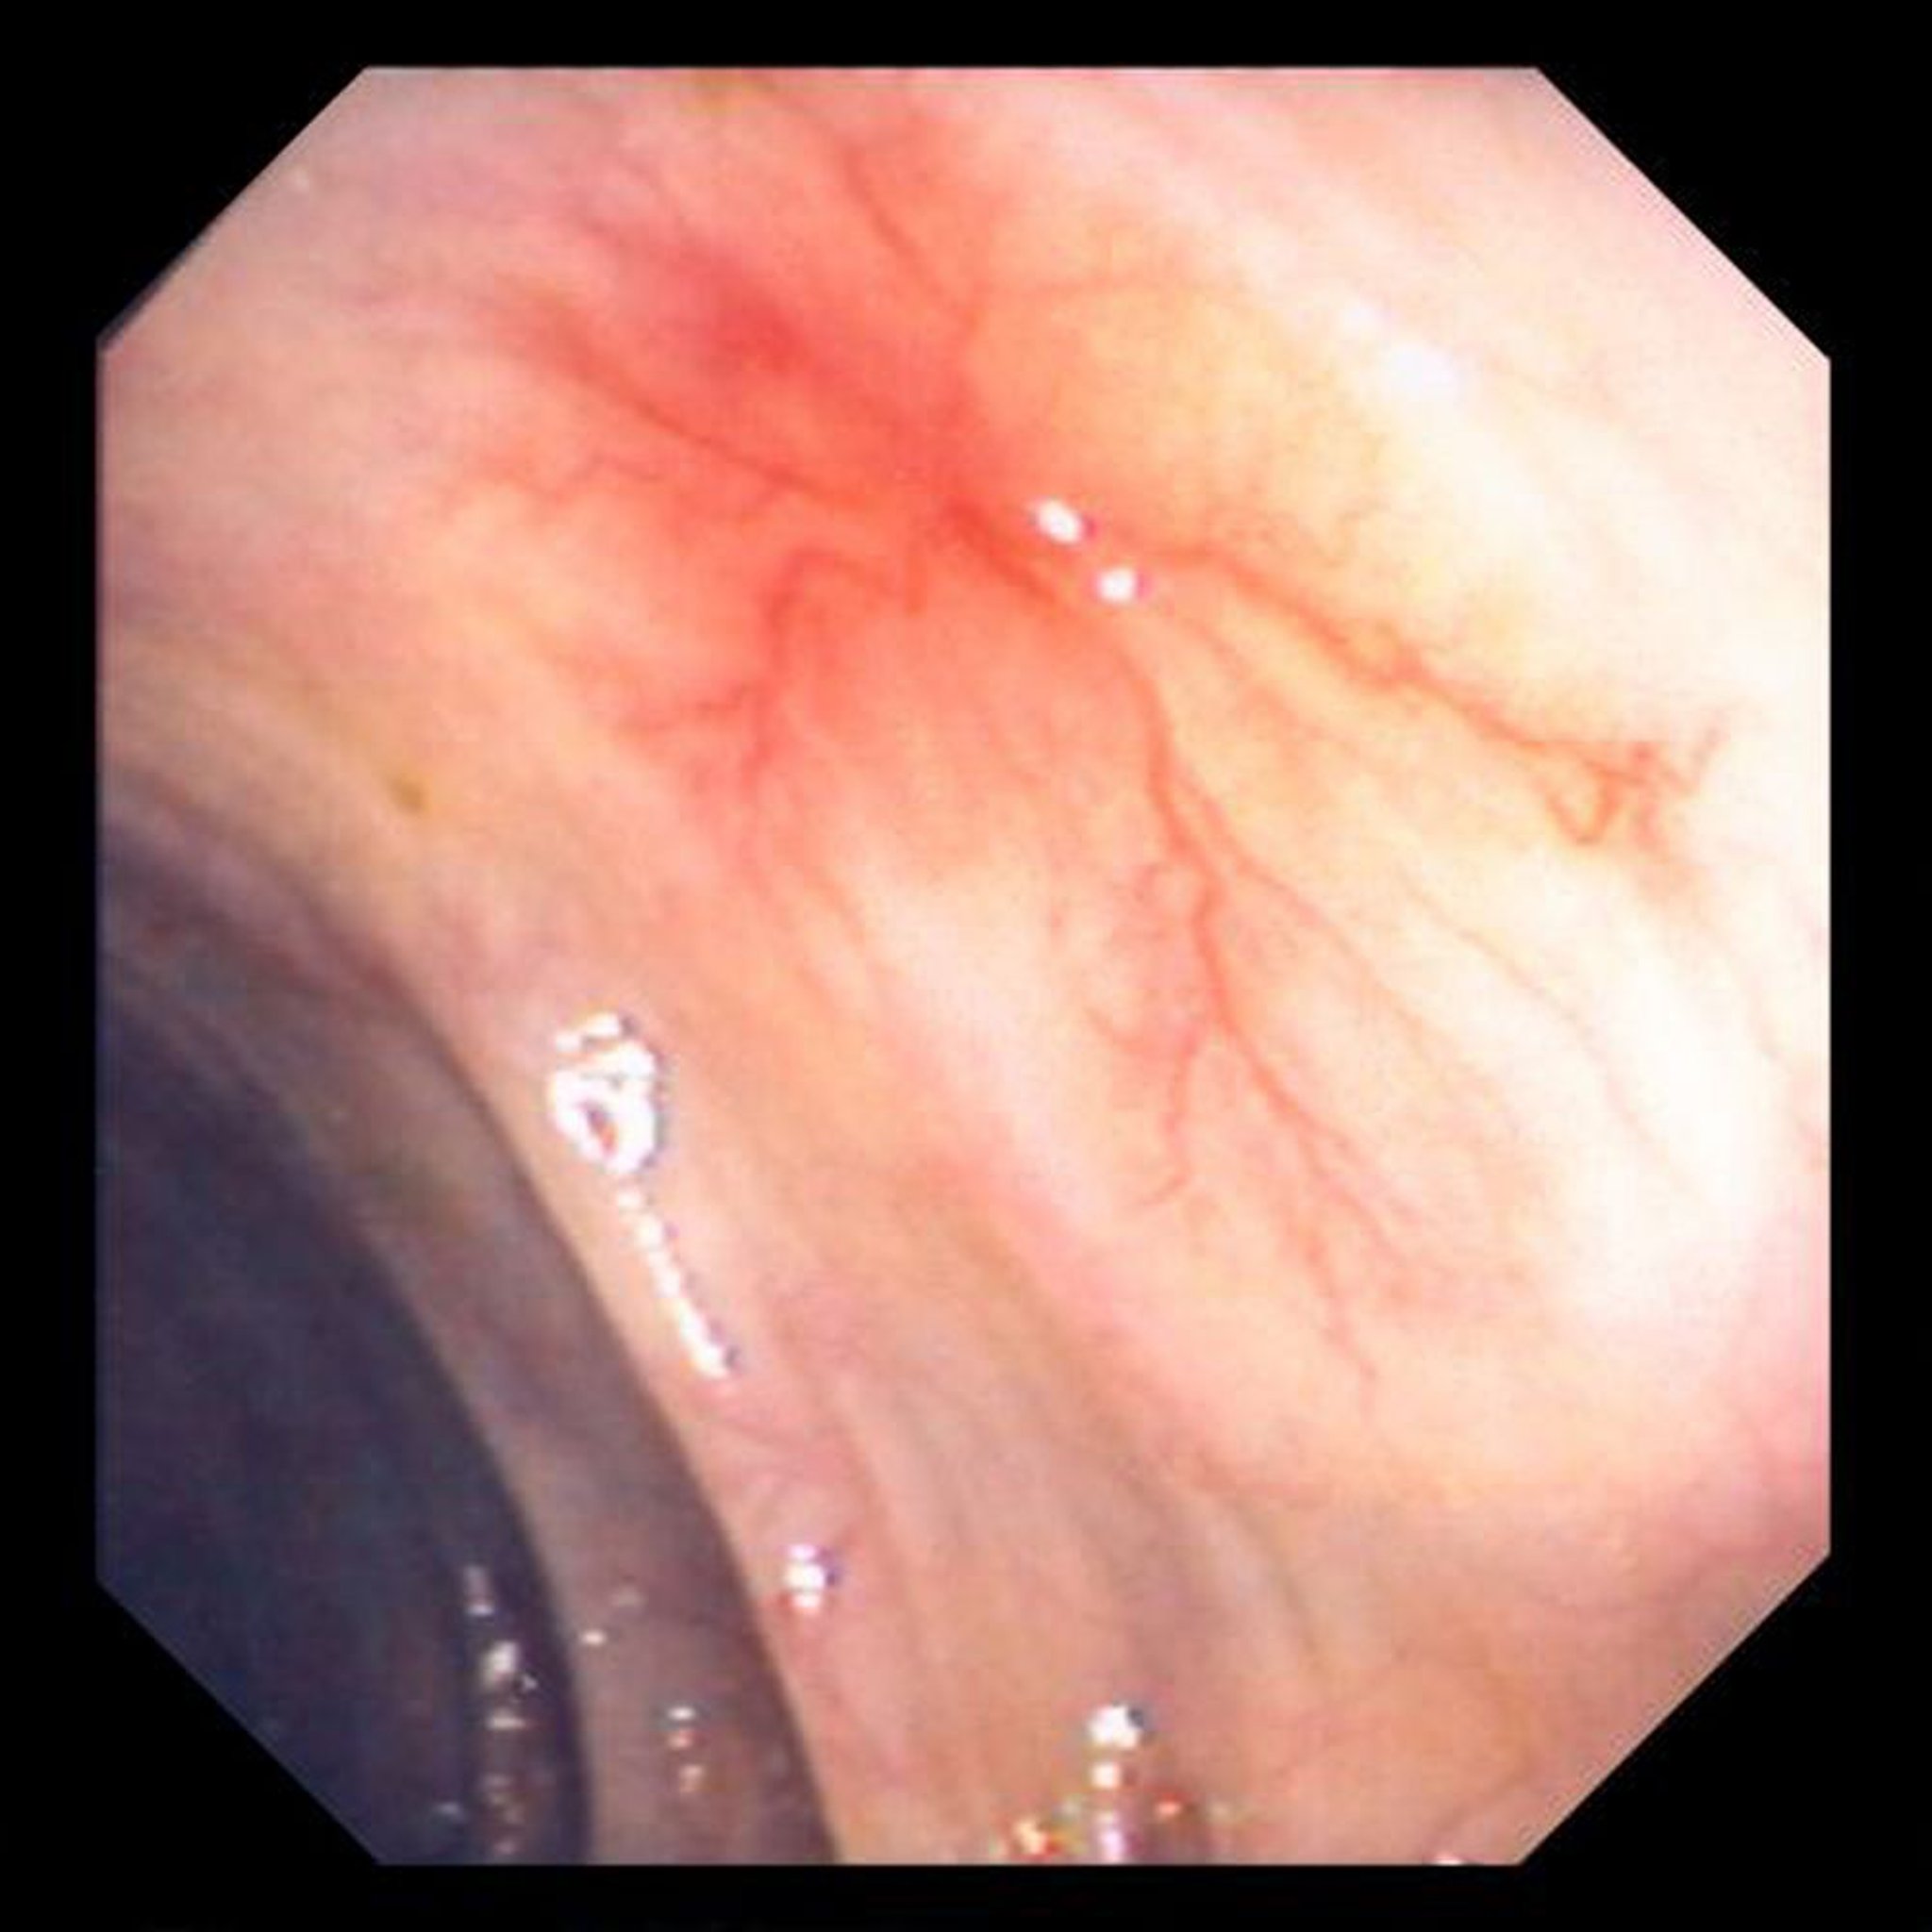

Alterazioni vascolari (angiodisplasia) nell’intestino

Questa immagine mostra un vaso sanguigno anomalo nella parete intestinale.

Immagine fornita dal Dott. David M. Martin.